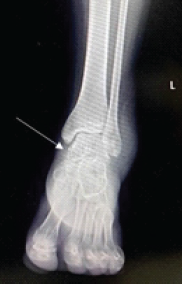

Cedell’s Fracture of the Talus Managed with Herbert Screw Fixation through Posteromedial Approach – A Case Report

Rajath S. Shetty , Shubham Y. Dakhode , Jaideep Das , Ajit S. Rathod , Aakash N. Varma , Abhishek M. Ganacharya

………………………………p.66-69